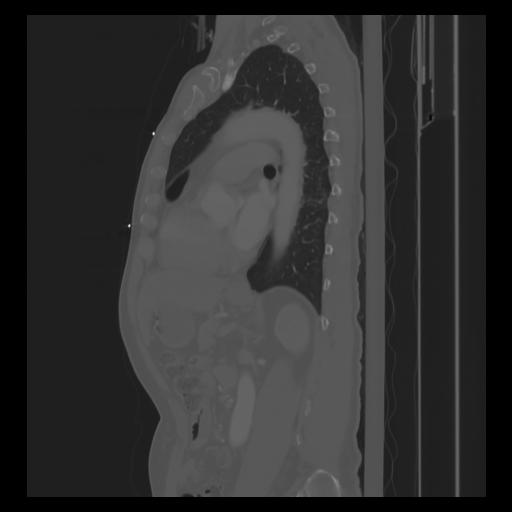

30 CUERPO,CE,Sagittal,3.000,CUERPO,Sagittal,